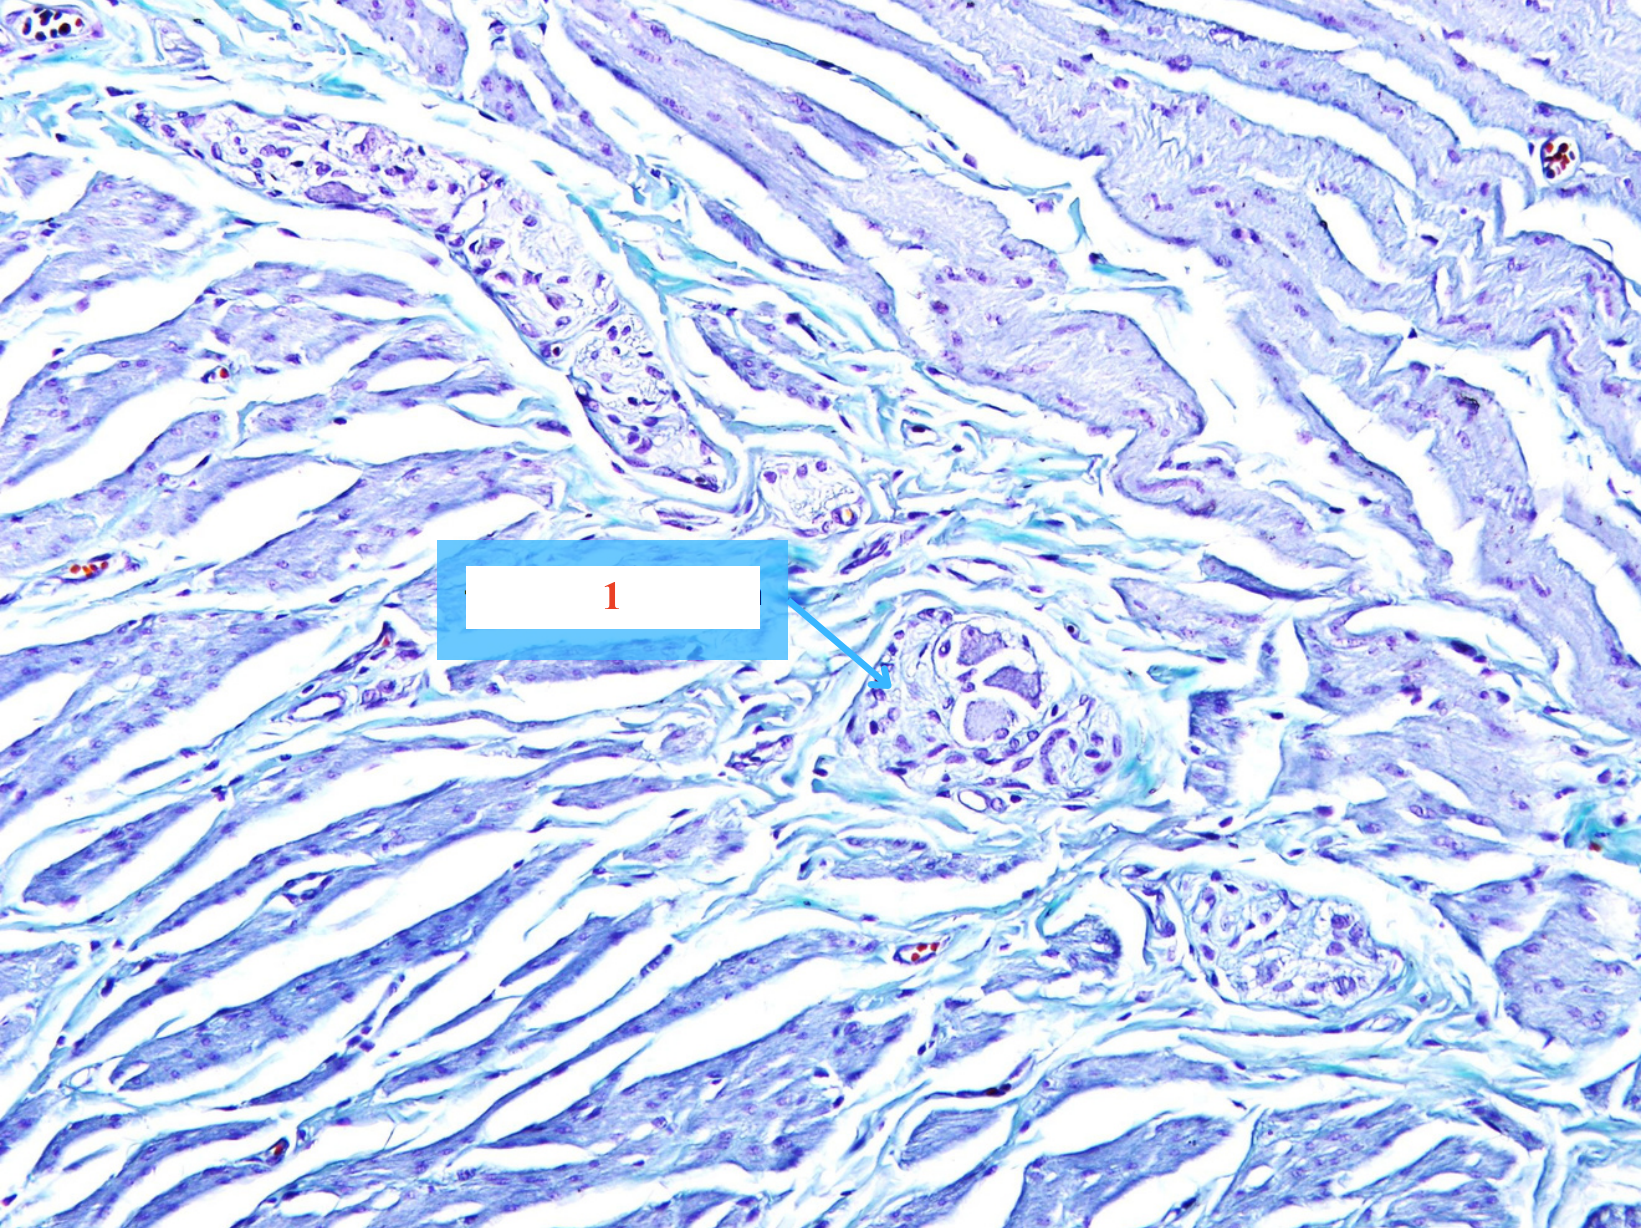

Cấu trúc gì ?

Bao bó thần kinh

Bao ngoại thần kinh

Mô nội thần kinh